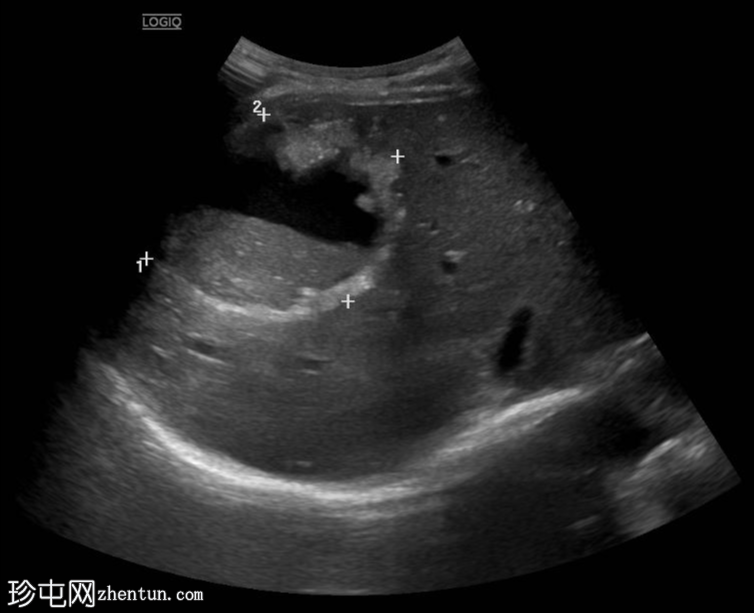

超声检查

4.png

纵向

位于肝段VIII中心的异质性肿块,其特征为不规则的高回声边缘、内部粗钙化以及中心低回声至无回声的液-液平面。还可见多个较小、边界清晰的高回声卫星灶。